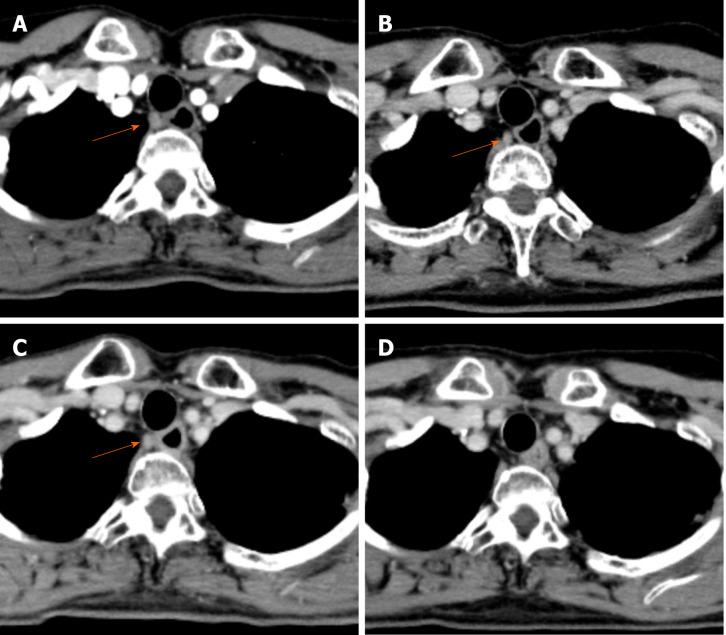

We report a successful case of a 59-year-old female with unresectable locally advanced T4 ESCC treated by two additional courses of chemotherapy with CF after induction chemotherapy with docetaxel, cisplatin and fluorouracil (DCF) followed by dCRT. Initial esophagogastroduodenoscopy (EGD) detected a type 2 advanced lesion located on the middle part of the esophagus, with stenosis. Computed tomography detected the primary tumor with suspected invasion of the left bronchus and 90° of direct contact with the aorta, and upper mediastinal lymph node metastasis. Pathological findings from biopsy revealed squamous cell carcinoma. We initially performed induction chemotherapy using three courses of DCF, but the lesion was still evaluated unresectable after DCF chemotherapy. Therefore, we subsequently performed dCRT treatment (CF and radiation). After dCRT, prominent reduction of the primary tumor was recognized but a residual tumor with ulceration was detected by EGD. Since the patient had some surgical risk, we performed two additional courses of CF and achieved a clinically complete response. After 14 mo from last administration of CF chemotherapy, recurrence has not been detected by computed tomography and EGD, and biopsy from the scar formation has revealed no cancer cells.

我们报告了1例成功治疗的病例,患者为59岁女性,患有不可切除的局部晚期T4期ESCC,在接受多西他赛、顺铂和氟尿嘧啶(DCF)诱导化疗后,再接受两周期CF化疗,随后进行同步放化疗。最初的食管胃十二指肠镜检查(EGD)发现食管中段有一处2型进展期病变并伴有狭窄。计算机断层扫描发现原发性肿瘤,怀疑侵犯左支气管,与主动脉直接接触90°,并有上纵隔淋巴结转移。活检病理结果显示为鳞状细胞癌。我们最初采用三周期DCF进行诱导化疗,但DCF化疗后病变仍被评估为不可切除。因此,我们随后进行了同步放化疗(CF和放疗)。同步放化疗后,原发性肿瘤明显缩小,但EGD检查发现有残留肿瘤伴溃疡形成。由于患者存在一定的手术风险,我们又进行了两周期CF化疗,实现了临床完全缓解。在最后一次CF化疗后14个月,计算机断层扫描和EGD检查未发现复发,瘢痕形成部位的活检未发现癌细胞。